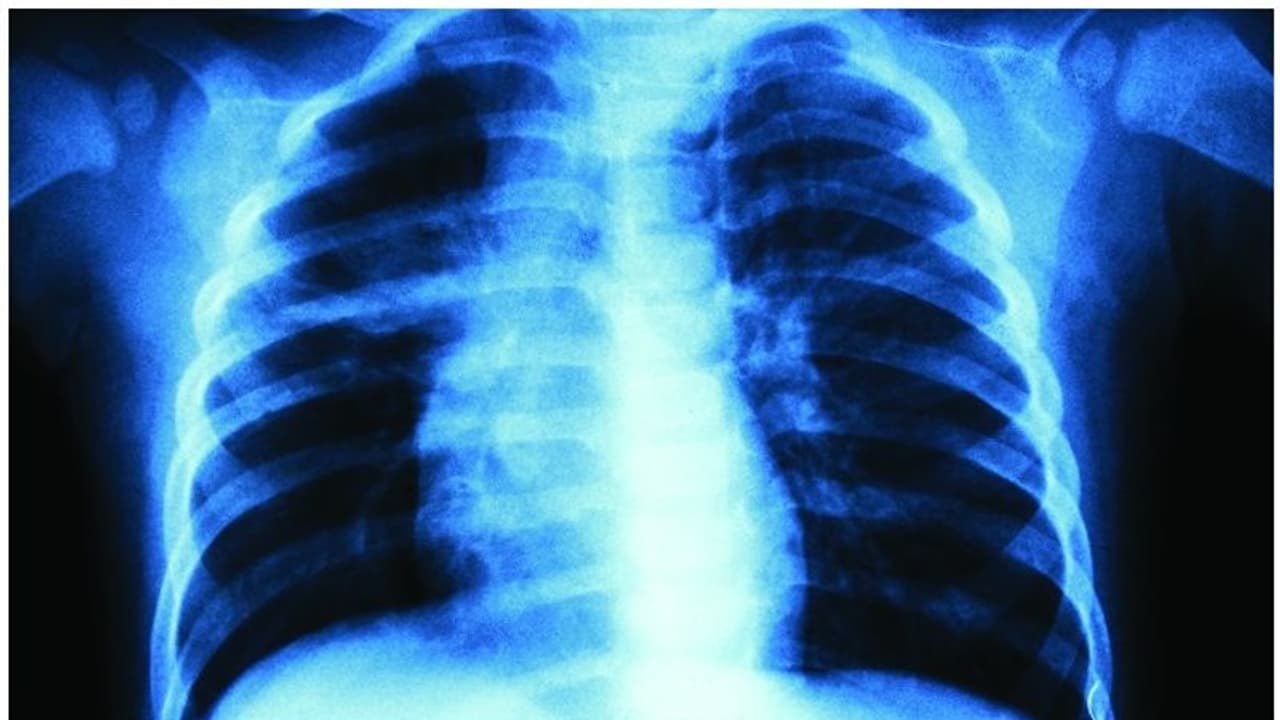

അമ്പലപ്പുഴ: വാഹനാപകടത്തിൽ പരിക്കേറ്റ് ആലപ്പുഴ മെഡിക്കൽ കോളജ് ആശുപത്രിയിലെത്തിച്ച യുവാവിന്റെ ഇടത് നെഞ്ചിന് പകരം വലതു നെഞ്ചിന്റെ എക്‌സ്‌റേ എടുത്തതായി പരാതി. പായൽക്കുളങ്ങരയിൽ വെച്ച് ബൈക്കിൽ കാറിടിച്ചാണ് യുവാവിന് പരിക്കേറ്റത്. നെഞ്ചിനും കാലിനും പരിക്കേറ്റ യുവാവിനെ നാട്ടുകാർ മെഡിക്കൽ കോളജ് ആശുപത്രിയിലെത്തിച്ചു. ഇടത് നെഞ്ചിൽ വേദനയുണ്ടെന്ന് അറിയിച്ചതിനെത്തുടർന്നാണ് ഡോക്ടർ എക്‌സ്‌റേ എടുക്കാൻ നിർദേശിച്ചത്. എന്നാൽ, എക്‌സ്‌റേ എടുത്തത് വലതു നെഞ്ചിന്റേതായിരുന്നു. പരിശോധനയിൽ കുഴപ്പമൊന്നുമില്ലെന്ന് ഡോക്ടർ അറിയിക്കുകയും ചെയ്തു.</p><p>വേദന അസഹനീയമായതിനെത്തുടർന്ന് യുവാവിനെ തിരുവല്ലയിലെ സ്വകാര്യ ആശുപത്രിയിലേക്ക് മാറ്റി. ഇവിടെ നടത്തിയ പരിശോധനയിലാണ് എക്‌സ്‌റേ മാറിയ വിവരം തിരിച്ചറിഞ്ഞതും ഇടത് നെഞ്ചിൽ നീർക്കെട്ടുള്ളതായി കണ്ടെത്തിയതും. കാലിന് ഗുരുതരമായി പരിക്കേറ്റ യുവാവിനെ പിന്നീട് അടിയന്തിര ശസ്ത്രക്രിയയ്ക്ക് വിധേയനാക്കി